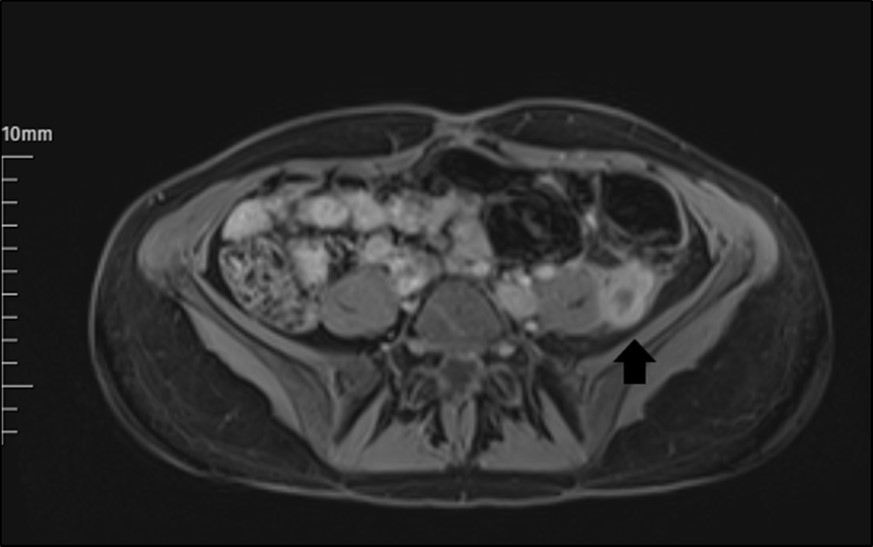

The abdomen and pelvis area were examined by MRI with contrast. It revealed a markedly dilated LOV containing abnormal soft tissue attenuation material throughout, indicating ovarian vein thrombosis. The aspect of a LOV in MRI images was persistent, with signs of increased signal in this area (Figure 1). Subsequent inferior abdominal MRI demonstrated a thrombus starting from the LOV to the level of the left renal vein. There is an enhancement in the vein walls (thrombophlebitis).

Figure 1.The appearance of a left ovarian vein in MRI.

The appearance of a left ovarian vein in MRI.